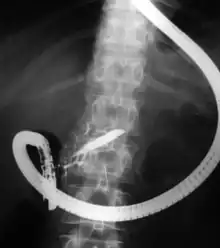

A dor associada com a síndrome pós-colecistectomia geralmente ocorre por espasmo do esfíncter de Oddi, presença de cálculos na via biliar principal, aderências pós-cirúrgicas, presença de um coto do canal cístico ou mesmo da vesícula biliar, pelo facto de, na ausência de vesícula se perder a função reservatório da bílis e esta drenar continuamente para o intestino.[2][3].